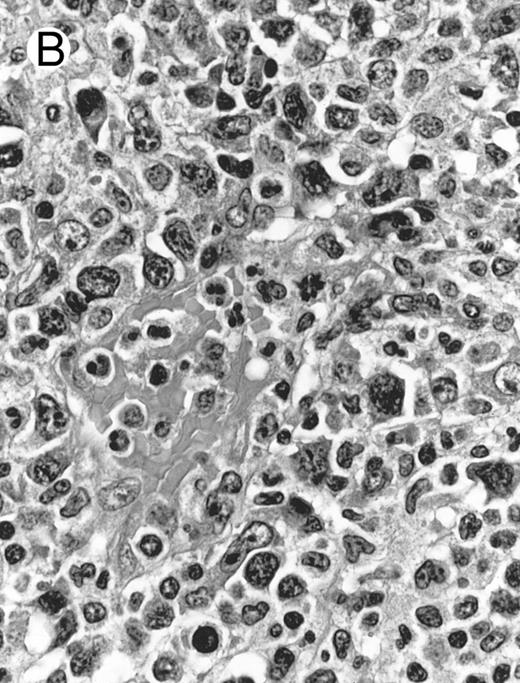

Histologically, the lymphomatous infiltrate was diffuse or patchy, with angiocentric and angiodestructive growth being observed in 30 cases (88.2%) (Figs 1 and 2). The cytologic composition was variable from case to case, including predominance of small cells, medium-sized cells, or large cells, or a mixture of these cell types (Fig 2 and 3). The tumor cell nuclei frequently showed irregular foldings and granular chromatin (Fig 2B). The larger cells possessed distinct nucleoli. The cytoplasm was moderate in amount and often pale. Karyorrhexis was usually prominent. Zonal tumor cell death, focal or confluent, was evident in 27 cases. In the 14 cases for which Giemsa-stained touch preparations were available, azurophilic granules could be identified in at least some of the neoplastic cells.

Laryngeal nasal-type NK/T-cell lymphoma relapsing as perforation of the terminal ileum (case no. 33). (A) The small bowel mucosa shows extensive necrosis and ulceration in the right field. There is also transmural lymphomatous infiltration. Note the vascular occlusion by lymphoma (arrow). (B) Higher magnification shows large and medium-sized lymphoma cells with irregular nuclear contours. The chromatin is fairly dense.